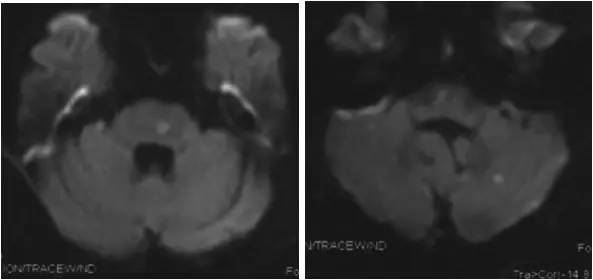

患者一个月前劳累后出现头晕,间断发作,每次持续约5-6分钟,可自行缓解。初未引起重视。其后因症状反复且程度加重,当地医院就诊,行MR提示桥脑及左侧小脑有新发梗死灶(图1)。

图1